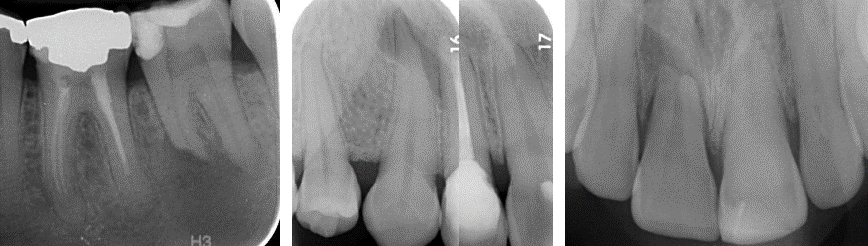

external surface resorption

clinical findings

radiographic findings

**PDL intact, no PA radiolucency **– no need for endo (used to preserve pulp, tx periradicular disease)

key feature of external surface resorption

A

PDL intact, no PA radiolucency

no need for endo

what has happened here

Trabecular pattern in area of resorption – healed, but still external surface resorption

Can be caused by

* Ectopic teeth – pressure from erupting tooth

* Pathological lesions - ameloblastomas

* idiopathic